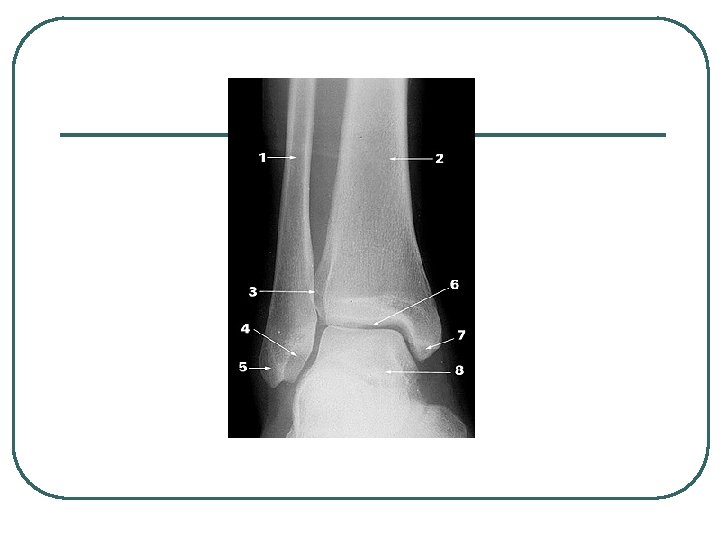

Ankle Sprains l l The medial malleolus is shorter than the lateral mallelous so there is naturally more inversion than eversion. Greater inversion increases the potential for overstretching of the lateral ligaments. Most sprains involve the lateral ligaments from excessive inversion. Deltoid ligament is sprained less often (25% of ankle sprains)

Lateral Collateral Ligament

Classification of Sprains l l 1 st Degree: • • Stretching of the ATFL little or no edema tenderness maintain function. 2 nd Degree • • • Partial tear of the ATFL and/or CFL moderate edema some function loss l 3 rd Degree • • • Complete tear ATFL, CFL, and/or PTFL total loss of function significant edema